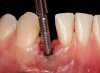

The crown and screw-retained custom abutment were removed, and a surgical cover screw was placed into the implant, thereby allowing spontaneous gingival augmentation in situ (Figure 33 and Figure 34). Note that the lingual aspect of the implant site was significantly more coronal than the labial aspect, which was positive because the defect would be limited to a facial–lingual defect. A fixed RBR bridge was cemented on the adjacent teeth and used as a tooth-supported transitional provisional restoration (Figure 35). A few weeks were allotted to let the soft tissue heal and migrate around the cover screw (Figure 36) to see if there would be complete coverage, thereby allowing a soft-tissue augmentation procedure to be performed with primary flap closure as in clinical scenario No. 2. The major obstacle in achieving a positive tissue response was that the implant depth was also deficient because the implant–abutment connection was at the level of the free gingival margin. It was decided that the best treatment option would be to remove the implant. A high-powered reverse-torque device (Fixture Remover Kit, NeoBiotech, www.neobiotechus.com) was used to remove the implant atraumatically (Figure 38 through Figure 41). The implant socket was allowed to heal for several months not unlike an extracted tooth (Figure 42). A new implant was placed in a better position from both a restorative and esthetic perspective (Figure 43), and after a few months of healing, a new crown was made (Figure 44). A satisfactory functional and esthetic result was achieved (Figure 45 and Figure 46) without employing pink porcelain.

Fig 33. Excessive facial angulation of the implant placement shown with an abutment driver in the access screw hole.

Fig 34. A surgical cover screw was placed in an attempt to decoronate the implant and gain soft-tissue coverage in situ.